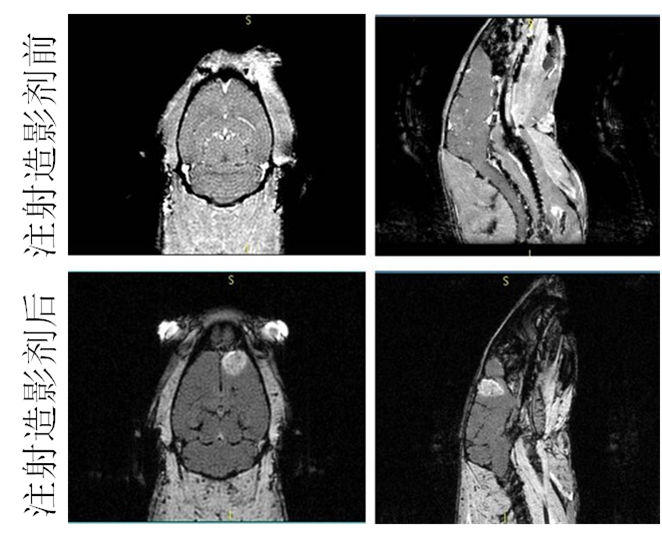

磁性纳米材料作为磁共振(MRI)造影剂的应用